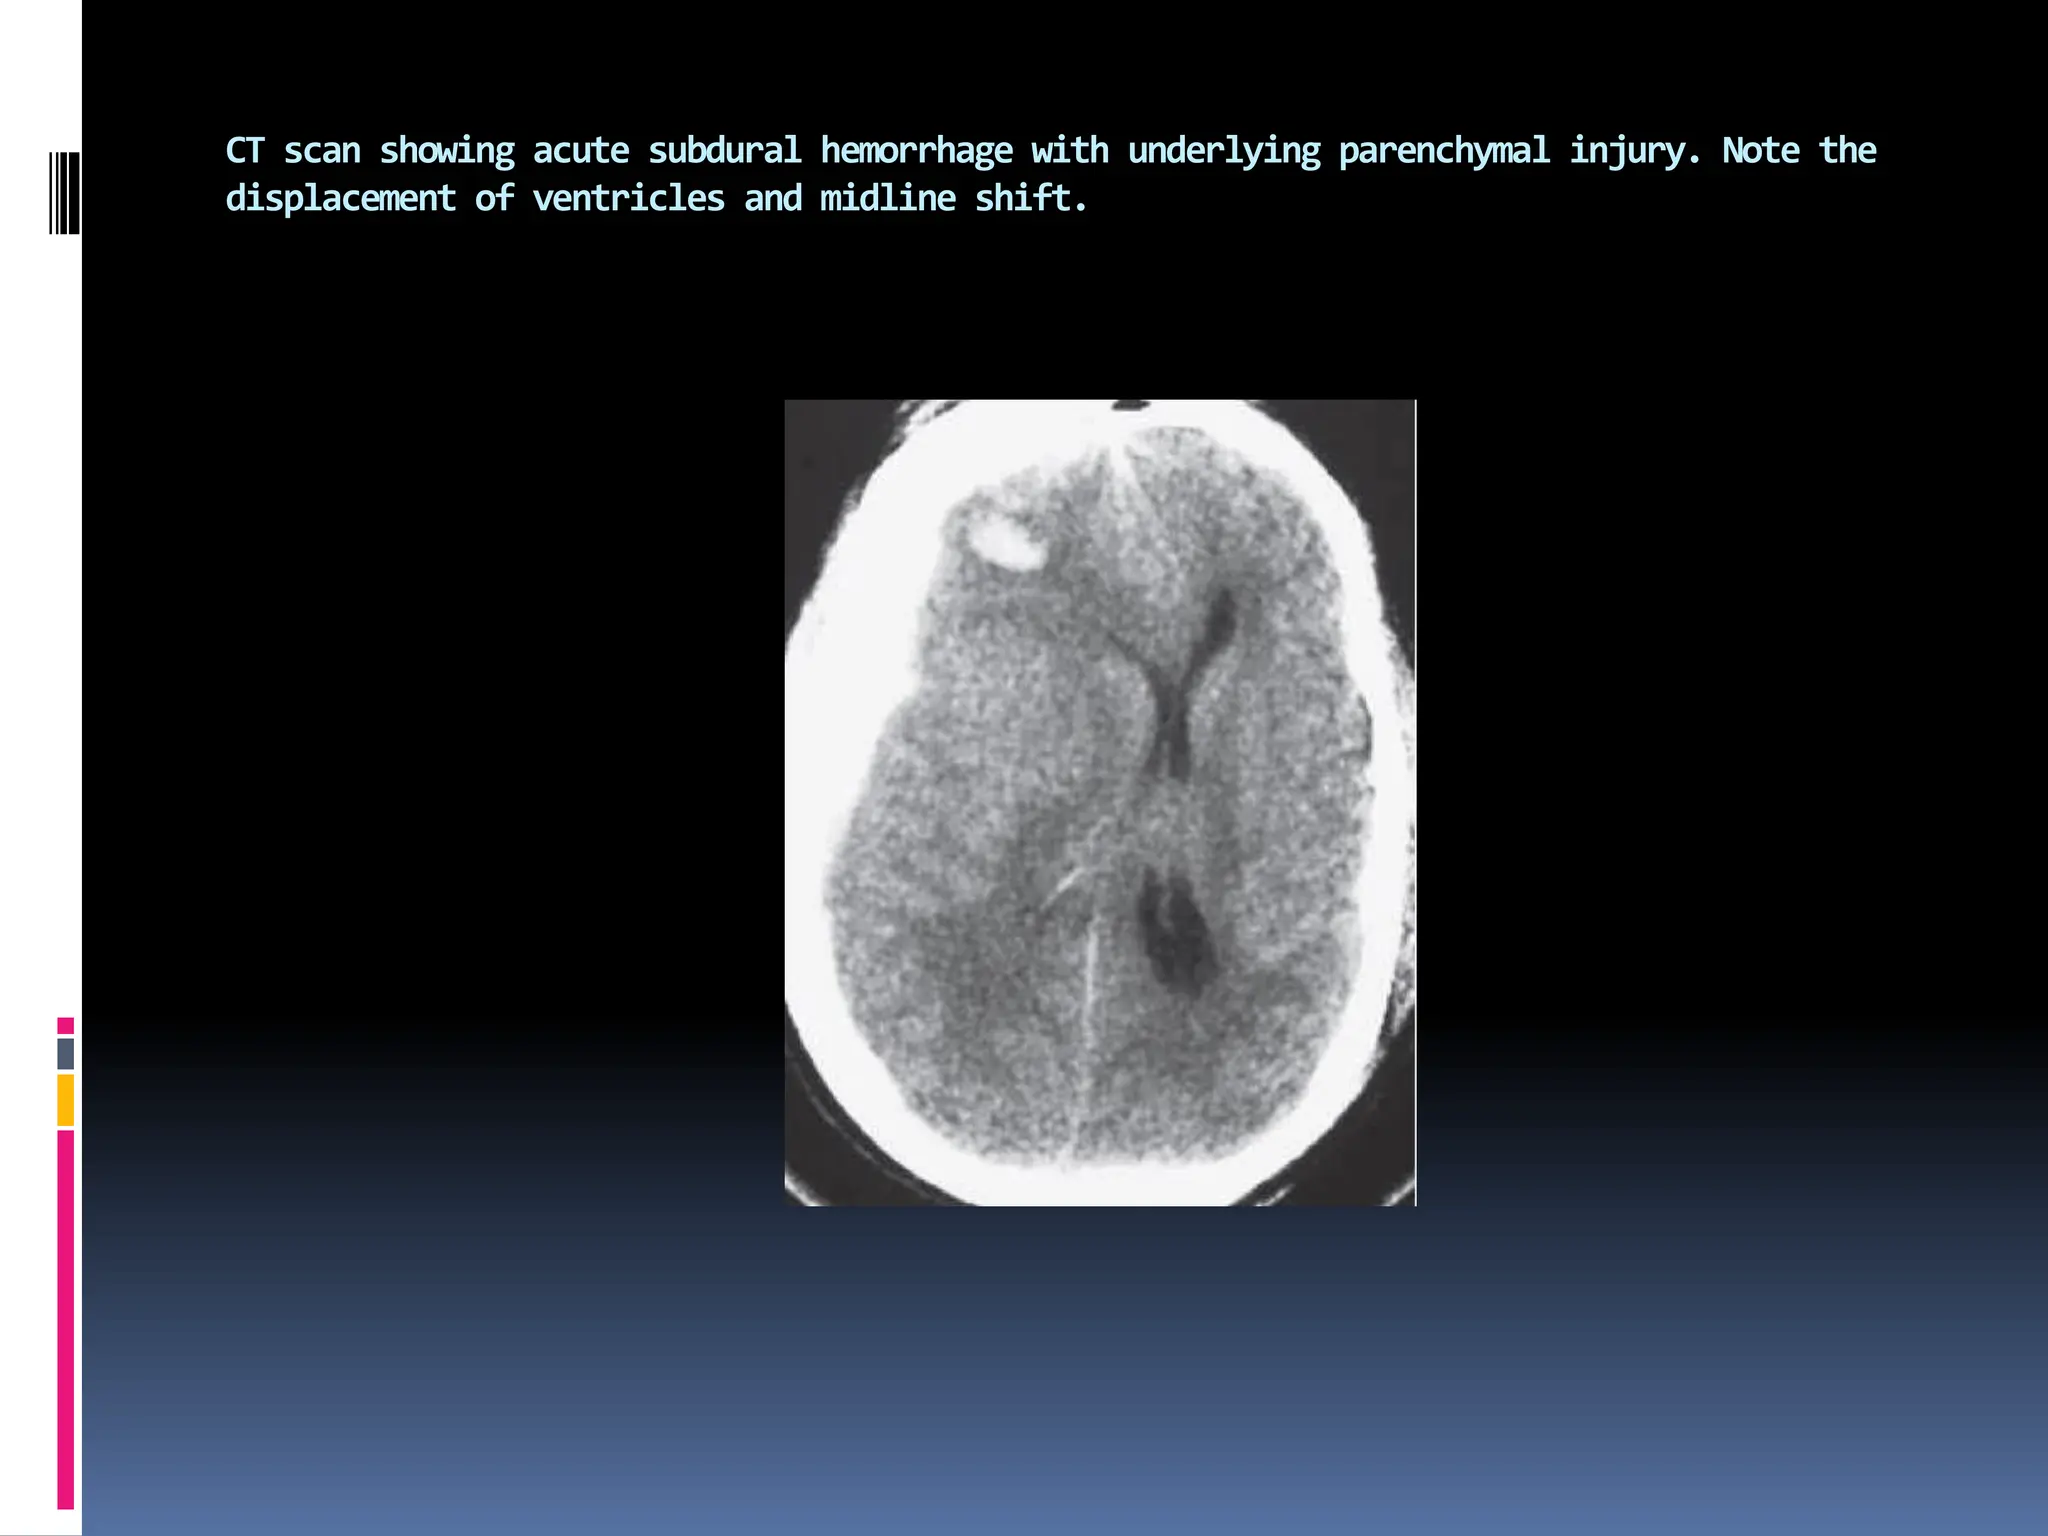

CT scan showing acute subdural hemorrhage with underlying parenchymal injury. Note the

displacement of ventricles and midline shift.